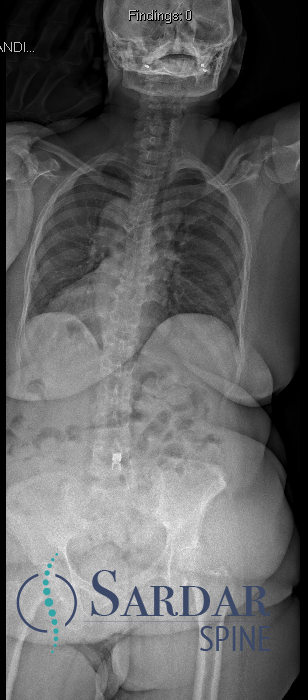

Case 1, Part 2: The patient had a #Vertiflex procedure done elsewhere; symptoms worsened, now can't stand upright, uses walker. Thoughts on her treatment so far? Next steps? #MedTwitter #Orthopedics #orthopedicsurgery #neurosurgery #spine #spinehealth #spinesurgery #scoliosis

55F with back pain and neurogenic claudication. Despite PT and epidural injections, relief is temporary. Difficulty walking long distances due to pain. What treatment would you offer next? #MedTwitter #SpineHealth #NeurogenicClaudication #spine